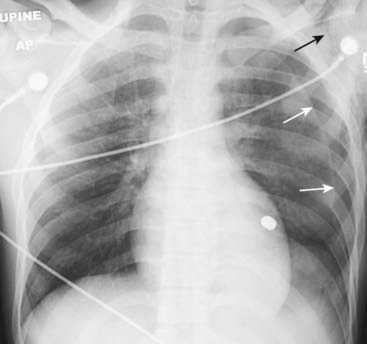

Figure 8-4 Deep sulcus sign.

In the supine position, air in a relatively large pneumothorax may collect anteriorly and inferiorly in the thorax and manifest itself by displacing the costophrenic sulcus inferiorly while, at the same time, producing increased lucency of that sulcus (solid black arrow). This is called the deep sulcus sign and is an indication of a pneumothorax on a supine radiograph. Notice how much lower the left costophrenic sulcus appears than the right sulcus (solid white arrow).